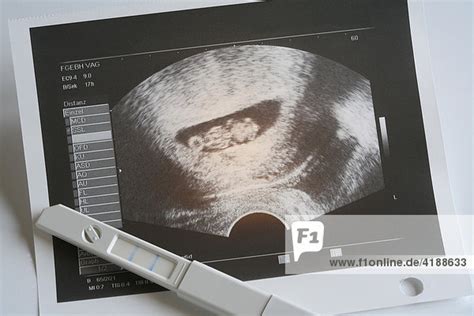

5. Schwangerschaftswoche: Sichtbarkeit des Embryos

Zwischen der 5. und 8. SSW wird eine Schwangerschaft per Ultraschall festgestellt. In der 5. Schwangerschaftswoche ist eine winzige runde Struktur im Ultraschall zu erkennen. Der Embryo ist jetzt etwa zwei Millimeter lang und auf dem Ultraschall zu dieser Zeit oft noch nicht eindeutig zu identifizieren.

6. Schwangerschaftswoche: Erste Konturen

In der 6. Schwangerschaftswoche ist der Embryo als kleine Verdickung in der schwarzen Fruchtblase auf dem Ultraschallbild zu erkennen.